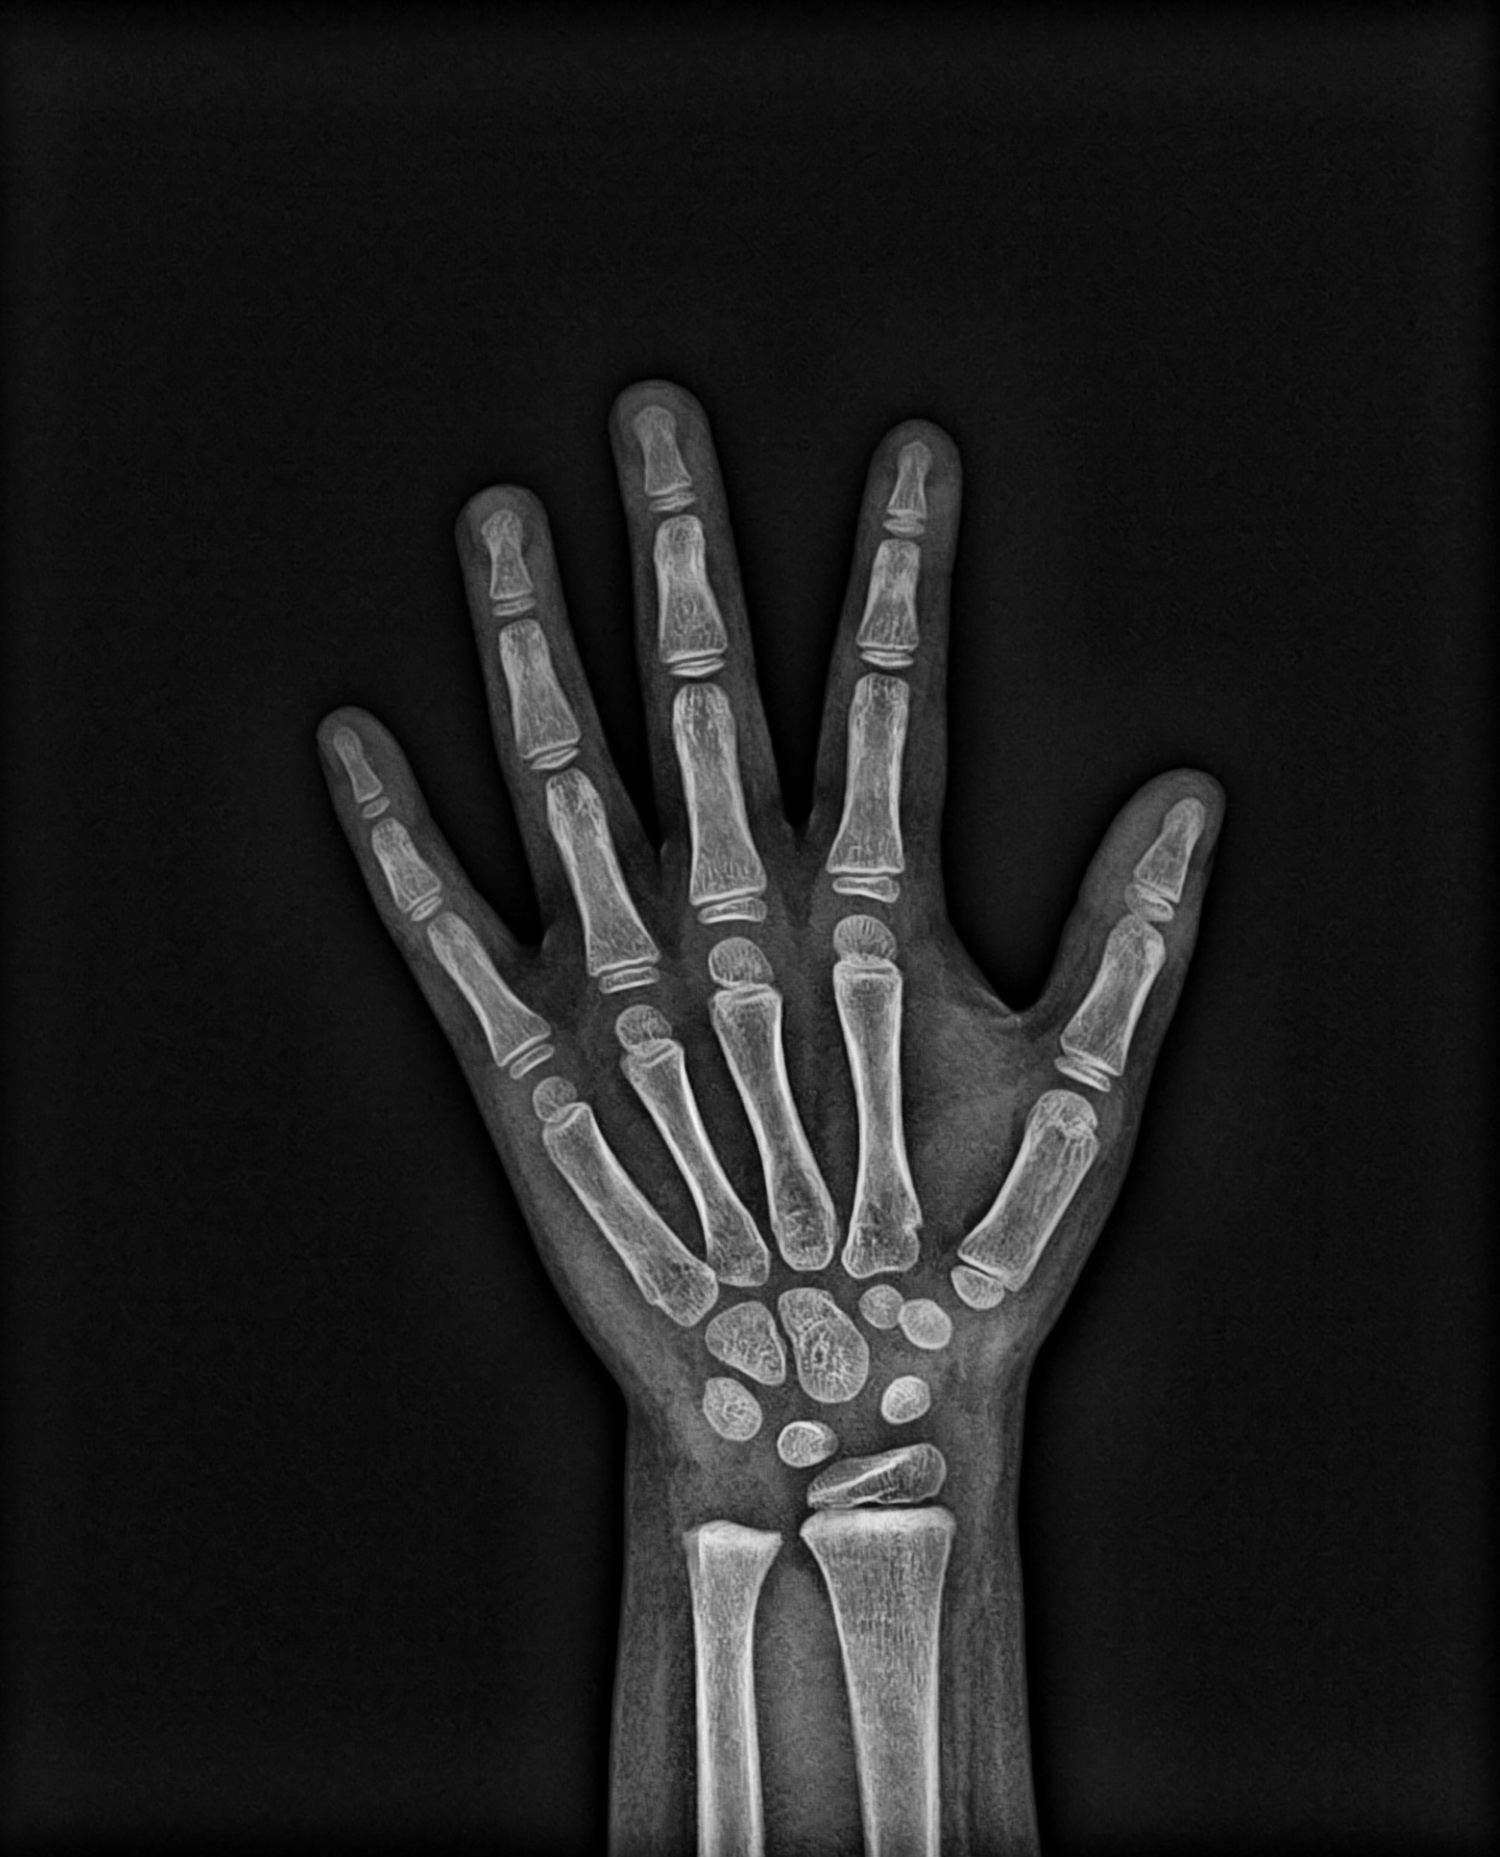

Punho e mão

ou carpal digital

Exame, onde se registram estruturas ósseas da mão e punho que fornecem informações sobre idade óssea do paciente.